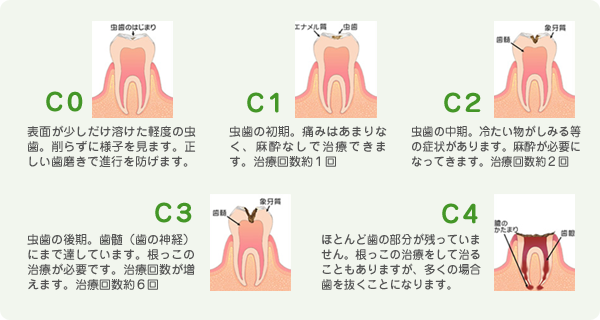

虫歯とは酸によって歯が溶かされる病気です。

虫歯の原因は「ミュータンス菌」という細菌です。この細菌が食べ物に含まれる糖分によって活発化し、歯垢(汚れ)を作り出し、その中に酸を作り出します。

残念ながら、虫歯が進行してしまった歯は自然治癒しません。そのまま放っておくと、悪化し、最後には歯を失ってしまいます。

予防と早期治療が大切です。痛くなってからではなく、定期的に歯医者さんに行きましょう!